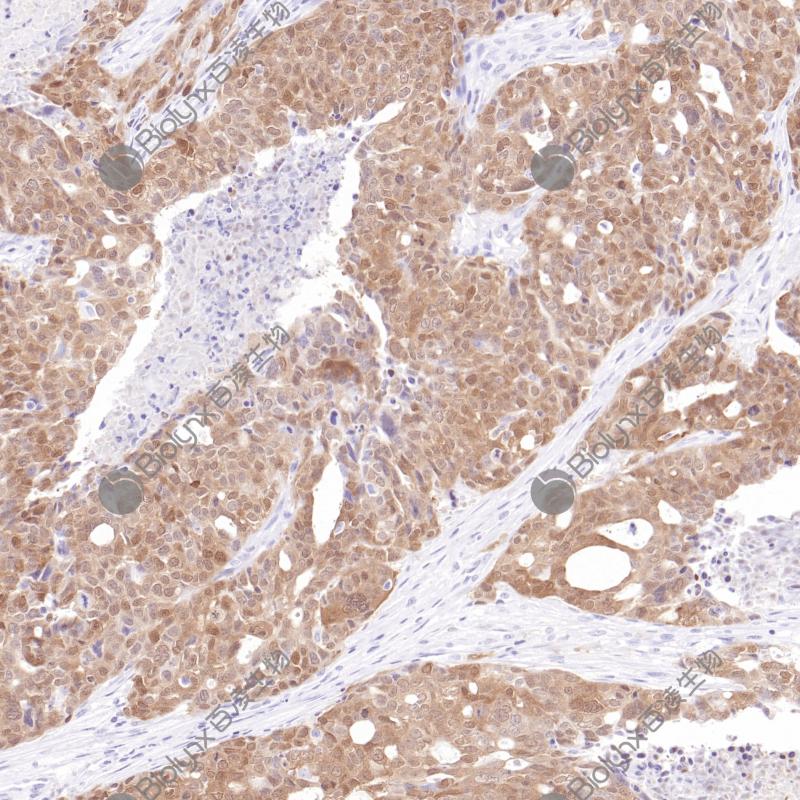

子宫内膜癌p16(BPM6238)染色

p16 INK4A(p16)是一种细胞周期蛋白依赖性激酶(CDKs)抑制剂,参与细胞周期的调控。当P16 INK4A基因发生缺失、突变等,不能抑制CDK4,最终导致细胞进入恶性增殖,加速肿瘤发生。p16 INK4A主要响应致癌基因表达、染色质断裂和各种压力胁迫等事件,这有利于受损细胞几乎无一例外地被衰老程序所捕获。因此,p16 INK4A的表达是常用的衰老细胞标志物。另外,p16 INK4A蛋白的高表达可作为宫颈癌细胞中的预测性生物标志物。

阳性对照

宫颈上皮内瘤变

亚细胞定位

细胞核